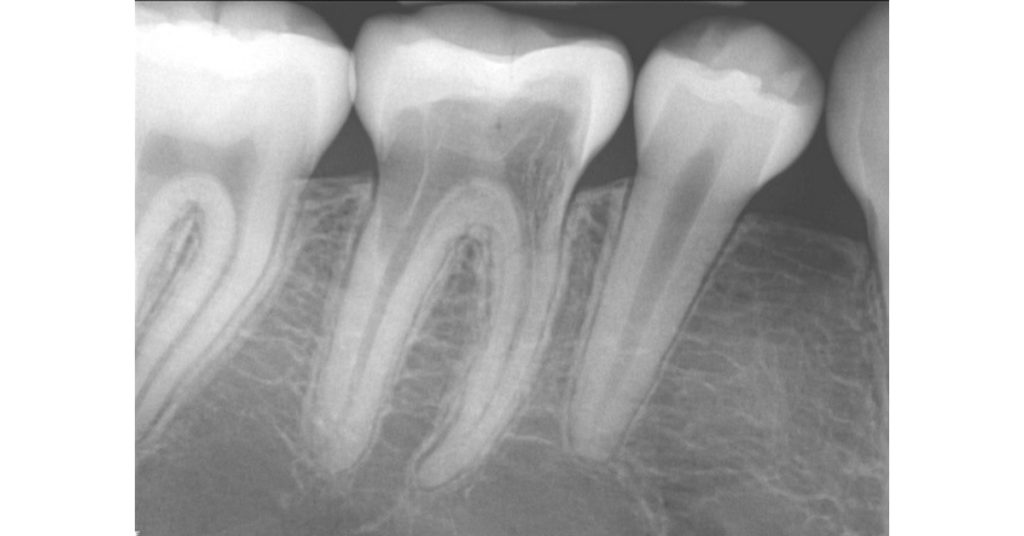

I’m not referring to replacement resorption, or ankylosis, which is typically seen after an avulsed tooth is replanted, nor the classic internal root resorption, but rather, “invasive cervical root resorption,” which is also known as “extra-canal invasive root resorption.” This type of root resorption starts on an external root surface, usually around the cervical level, progressively invading the root, going in a coronal and apical direction (Fig. 1).

What’s unique about this type of root resorption is that it does not invade the pulp. In fact, the pulp in these teeth remains vital, and the resorption tends to navigate around the pulp canal (hence the alternate designation of extra-canal invasive root resorption). Radiographically, even with extensive cases of invasive cervical root resorption, you can still visualize an intact canal space (Fig. 2).